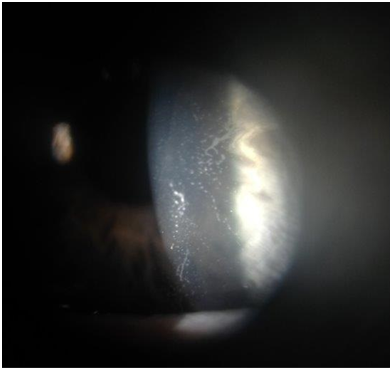

Figure 1Slit lamp photograph of left cornea demonstrating epithelial ingrowth under the midperiphery of the LASIK flap with direct extension into the visual axis.

Figure 2Slit lamp photograph of left cornea after surgical debridement of epithelial ingrowth and subsequent flap replacement

In the current case, epithelial ingrowth resolved on slit lamp exam after flap lift, debridement, and drop treatment; visual symptoms did not return. How the epithelial cells were introduced under the corneal flap remains unclear. Traumatic crystalline foreign bodies at the LASIK flap interface without flap displacement has been reported. Choi postulated that a sharp, high velocity, but weak ocular trauma could open the potential stromal space and leave debris without displacing the flap.20 We speculate a similar mechanism occurred with this patient or that the twig may have microscopically penetrated to the interface, implanting surface epithelial cells into the potential space. Cellular proliferation may have given the patient their presenting symptoms. Although corneal slit lamp examination is the standard for detecting epithelial ingrowth, anterior segment optical coherence tomography (OCT) may be a useful diagnostic tool. OCT may evaluate corneal structure changes related to disease before surgical debridement.21 After treatment, careful monitoring with close follow-up in these patients is necessary. Higher rates of recurrence even after surgical debridement have been reported.22 Post-traumatic epithelial ingrowth introduces cells into the corneal flap interface and corneal disturbance is observed. In this report, however, epithelial ingrowth occurred beneath the flap without any sign of disruption. This report exemplifies the need for close follow-up and examination of all LASIK patients even after minor trauma, since corneal anatomy is indefinitely altered. Ophthalmologists should educate patients on epithelial ingrowth as a post-operative complication and carefully monitor patients for signs, regardless of observed flap disruption or distant chronology from the initial LASIK procedure.